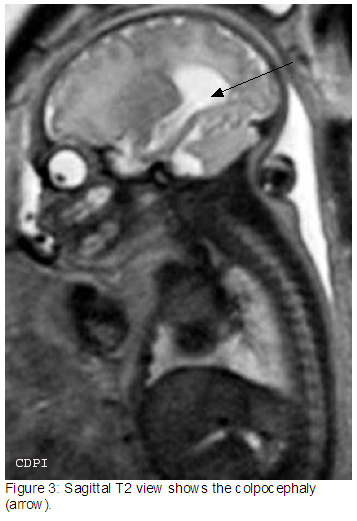

3. и 4. На саг. Т2 колпоцефалия (стрелка)